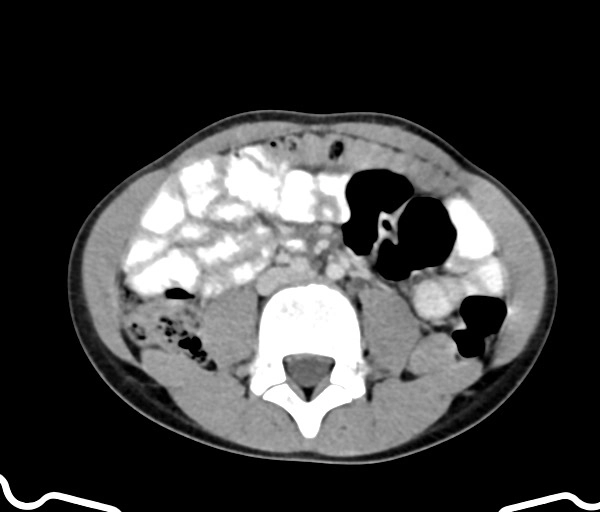

• Bệnh lý viêm nhiễm

Viêm bàng quang (Cystitis)